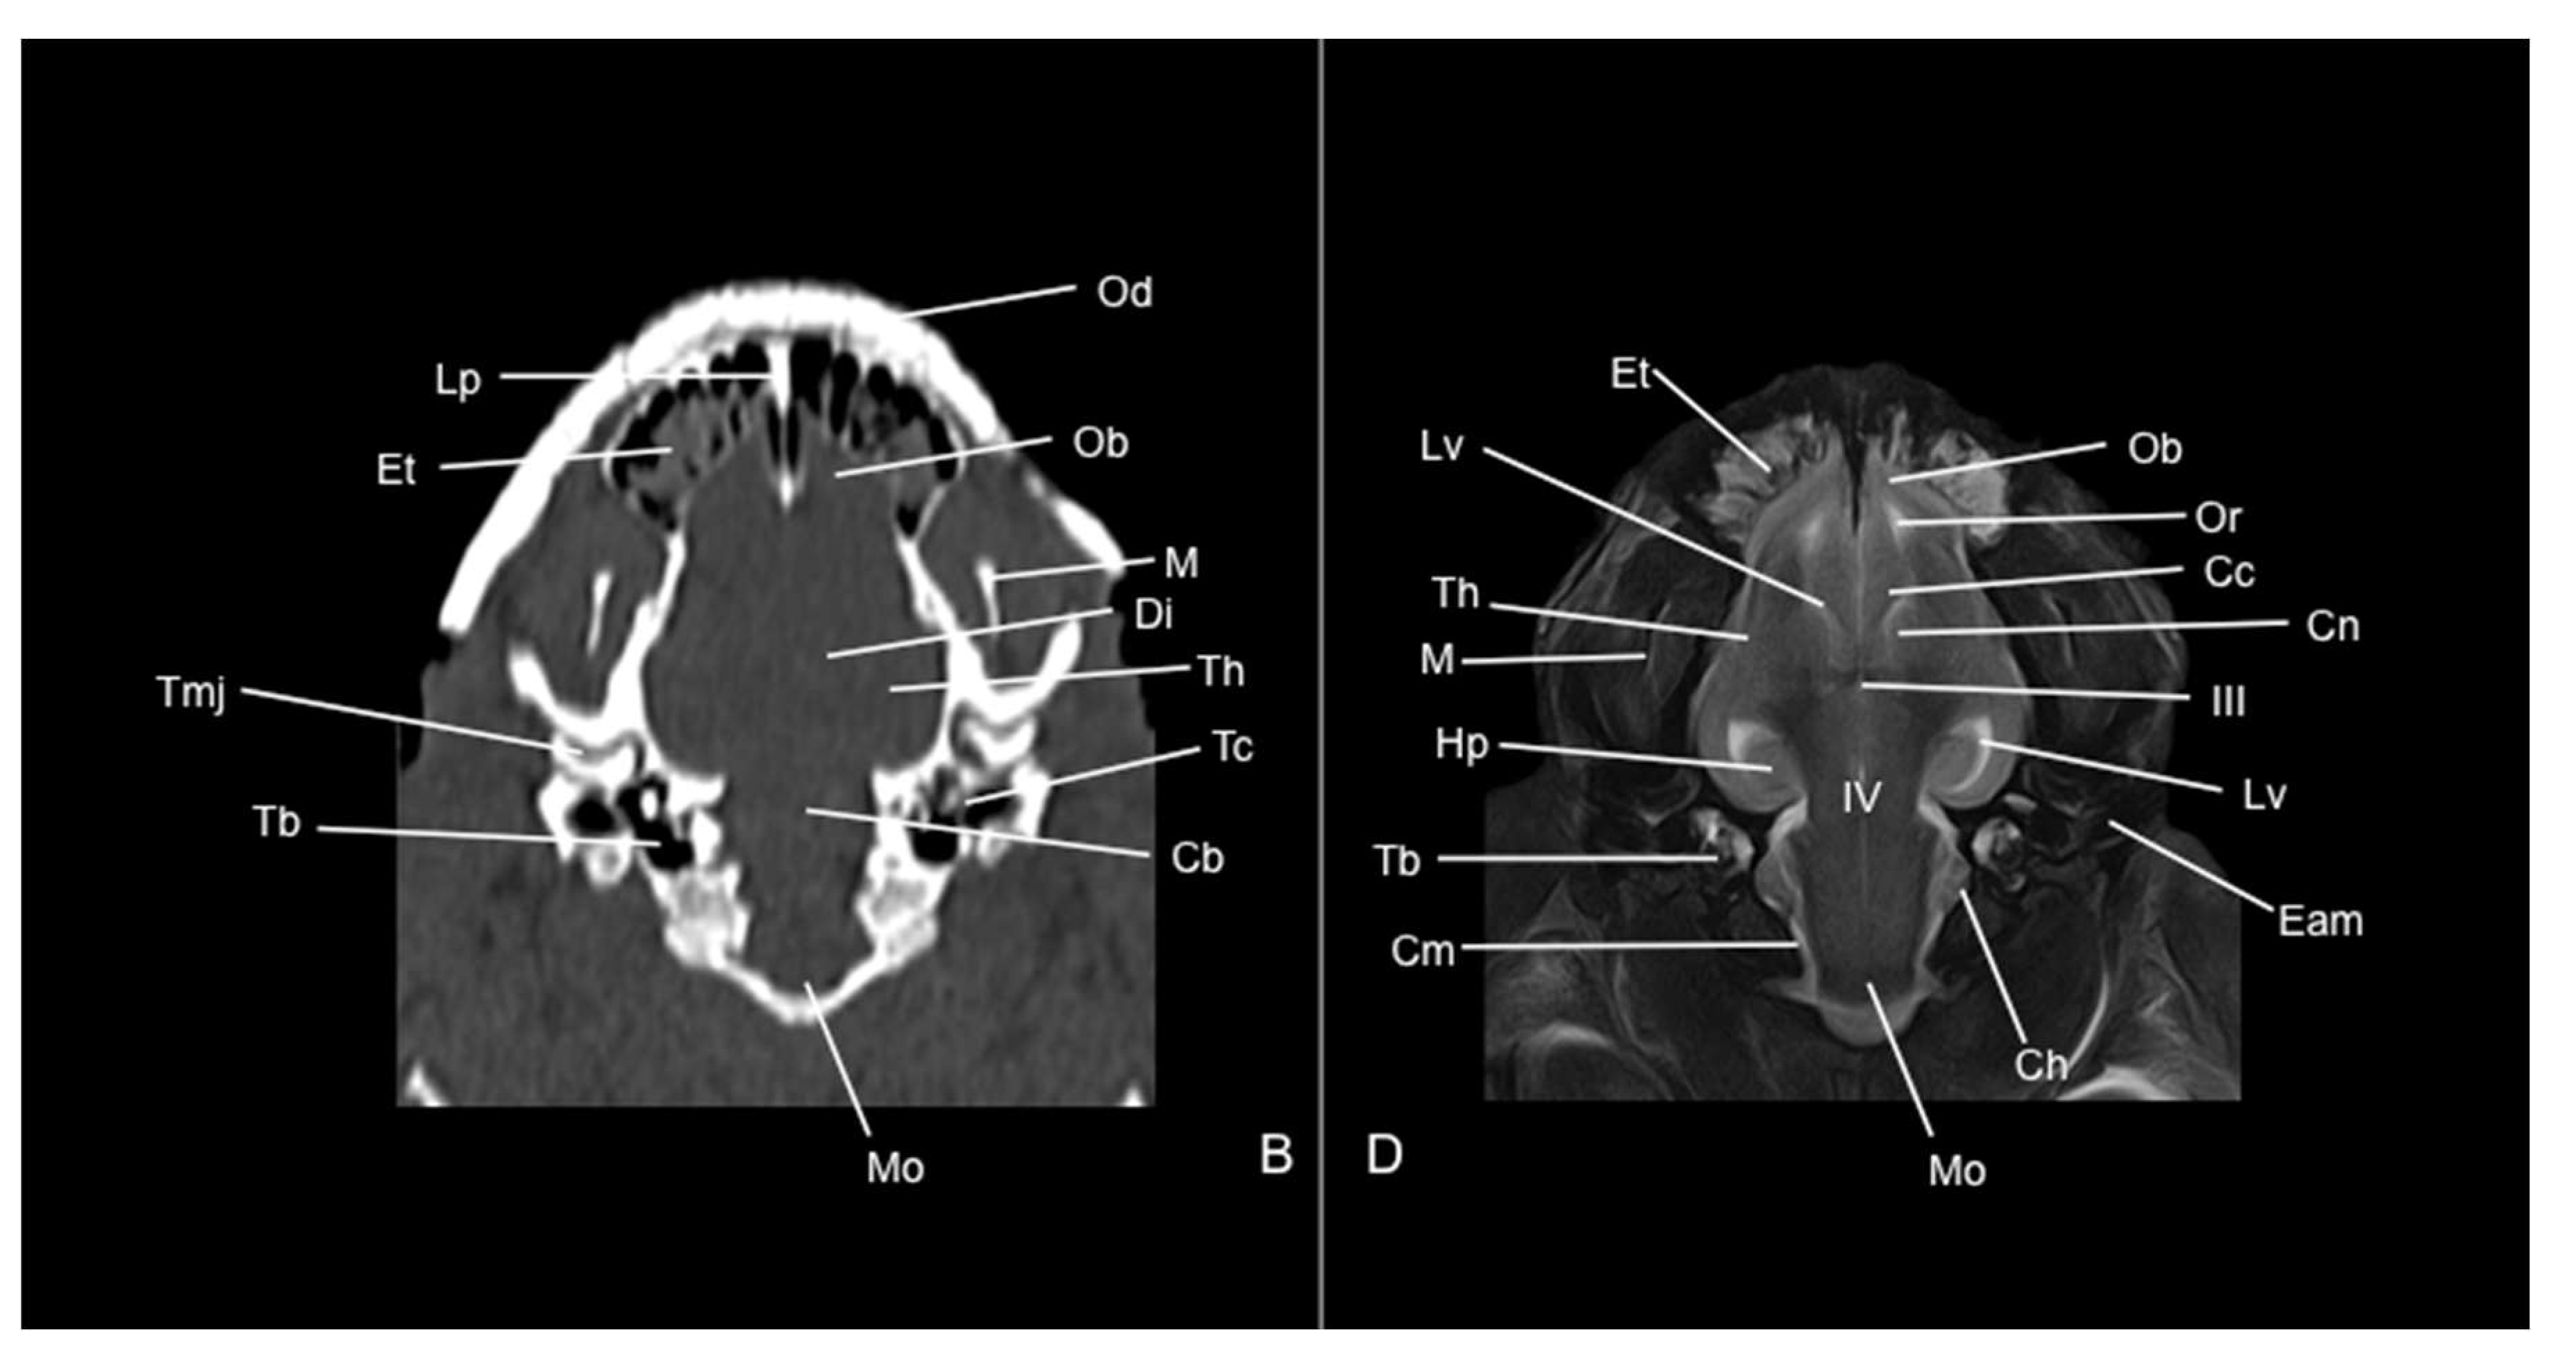

In this research, we have studied the head of the six-banded armadillo, applying advanced imaging techniques such as CT and MRI. Furthermore, by combining the images obtained through these techniques with anatomical cross sections, we present an adequate description of the structures that constitute the head of this species. This anatomical information could provide a valuable diagnostic tool for the clinical evaluation of different desorders in six-banded armadillo including skull malformations, fractures, and neoplasia.

3.2. Computed Tomography Study

3.3. Magnetic Resonance Imaging (MRI)